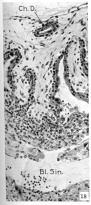

Section of tissues at the implantation site

Section 44-3-3

Section 44-2-2

Section 44-1-2

Section 42-2-5

Enlarged part of the preceding section

Chorionic duct

Cytotrophoblast

Cyst

Transition zone